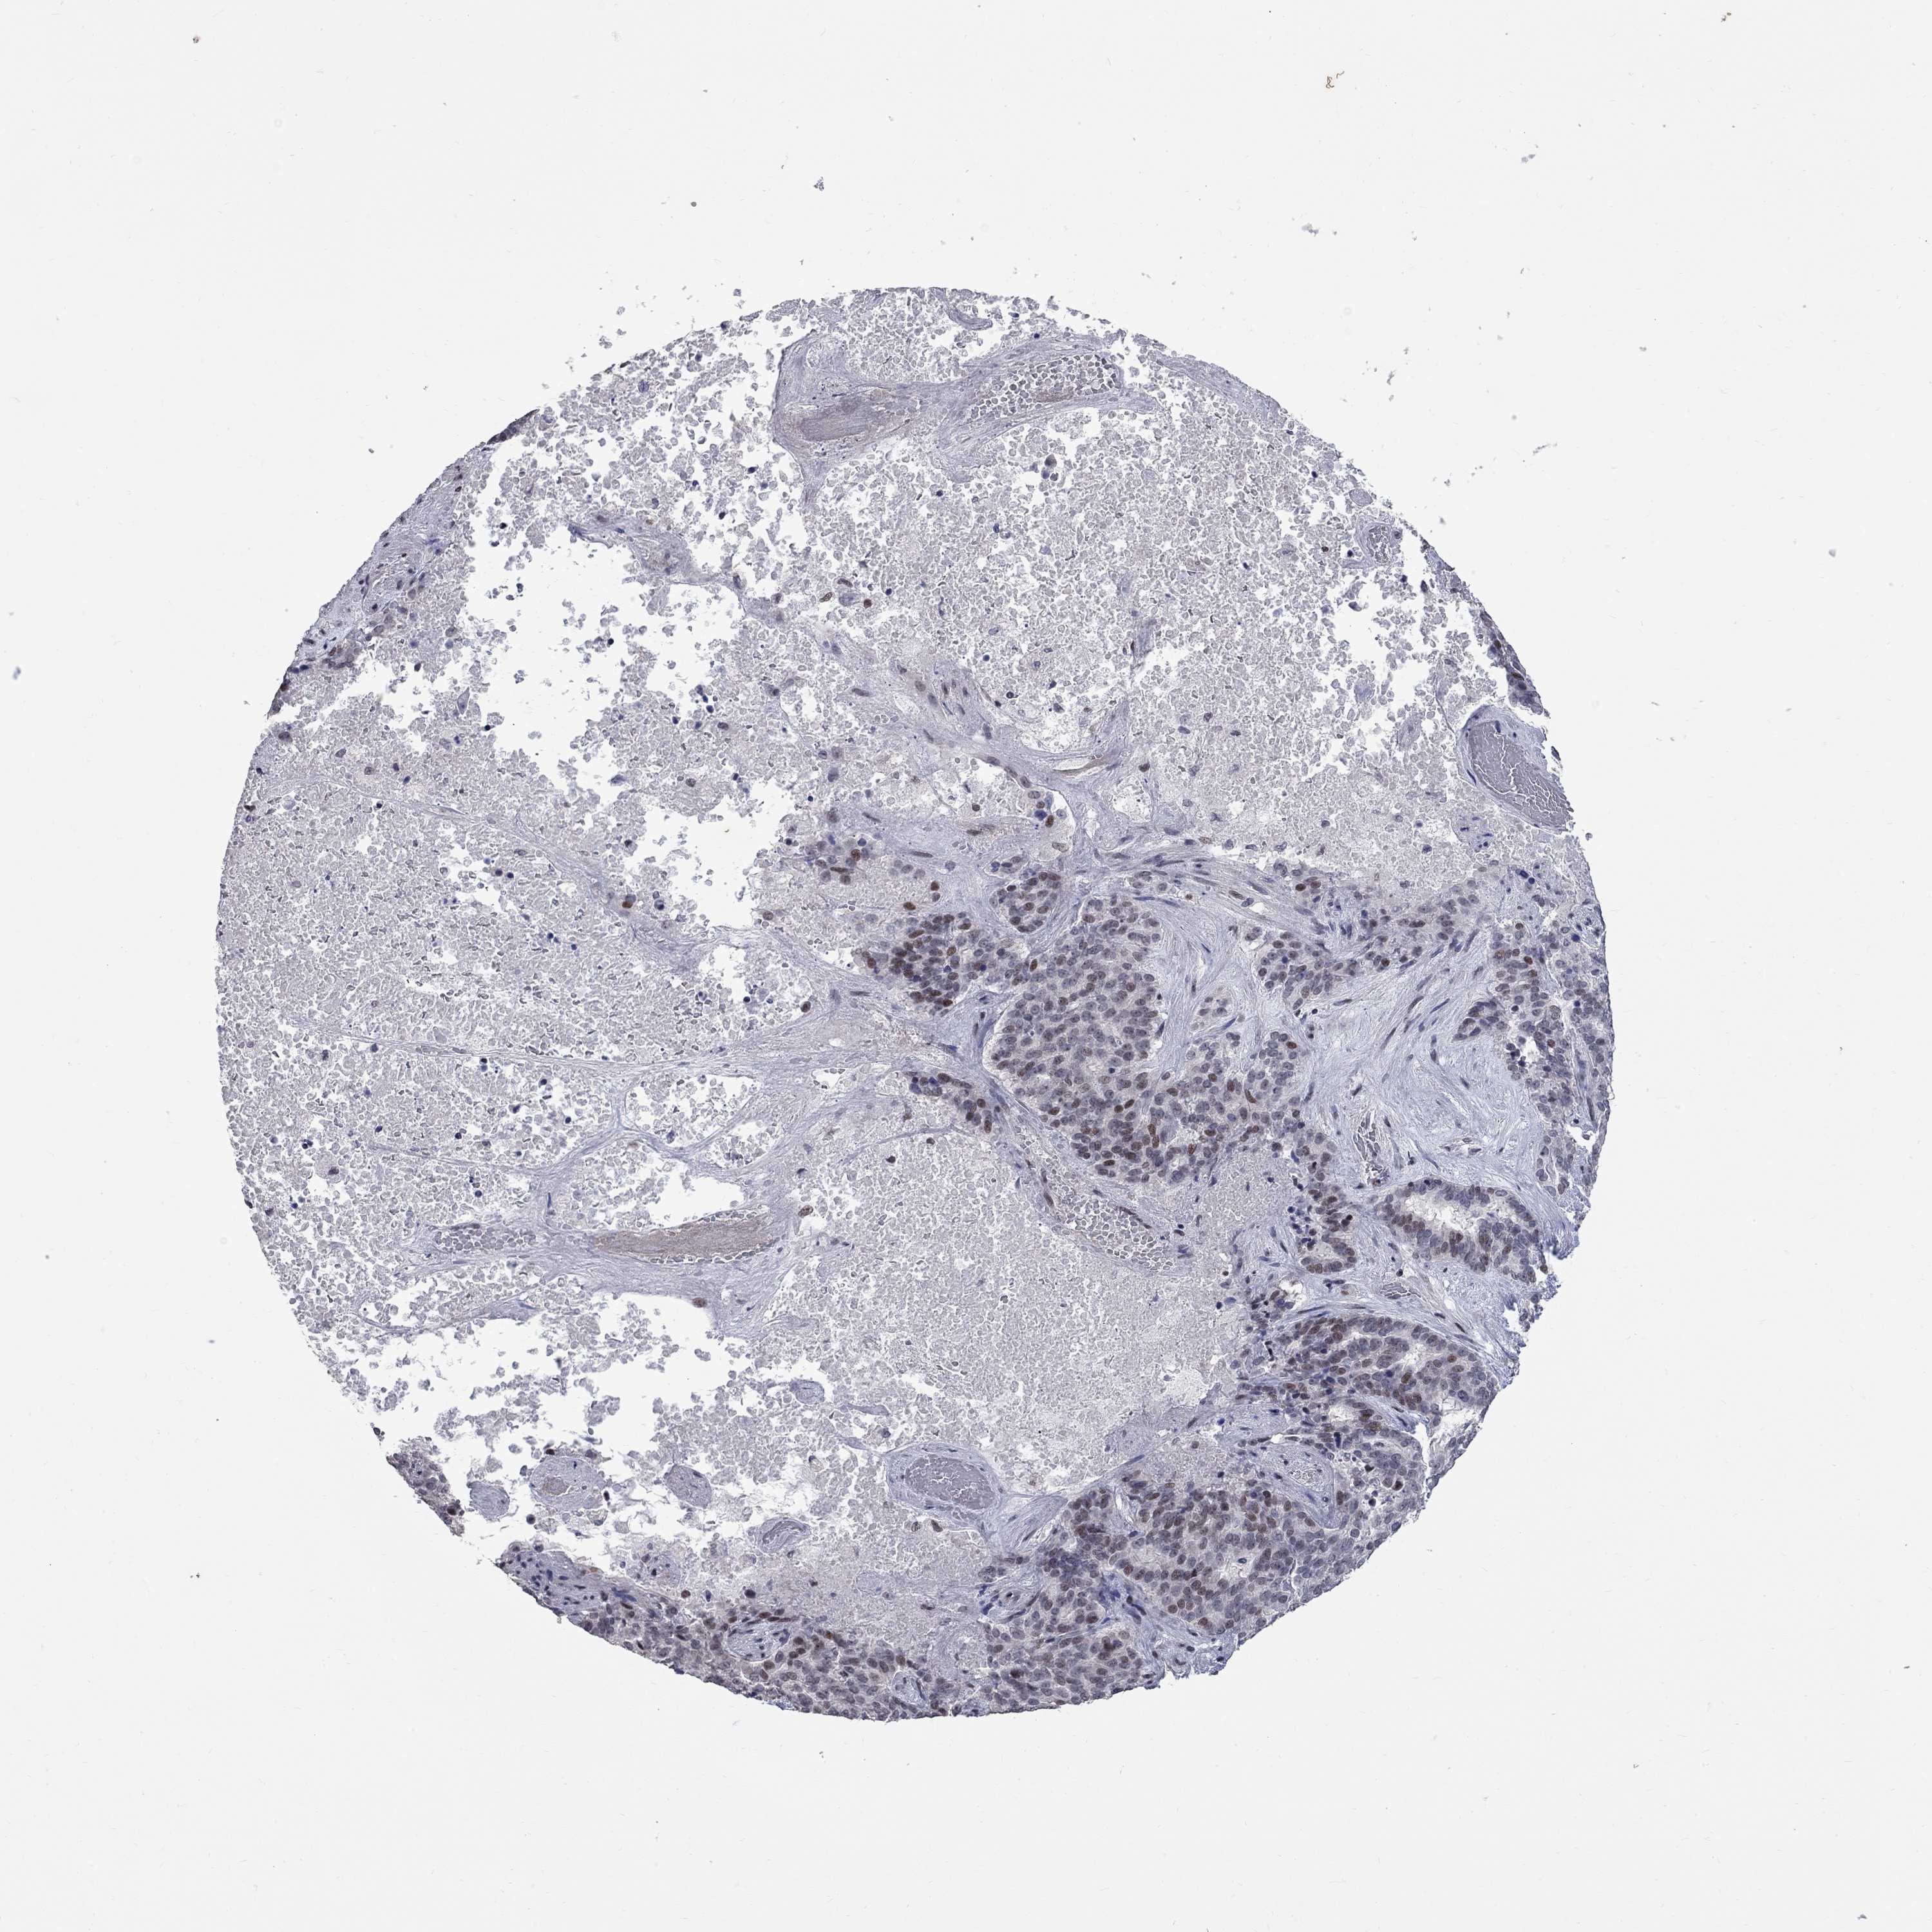

LIVER CANCER - Protein expressioni

A mouse-over function shows sample information and annotation data. Click on an image to view it in a full screen mode. Samples can be filtered based on level of antibody staining by selecting one or several of the following categories: high, medium, low and not detected. The assay and annotation is described here.

Note that samples used for immunohistochemistry by the Human Protein Atlas do not correspond to samples in the TCGA dataset.

Antibody stainingi

Antibody staining in the annotated cell types in the current human tissue is reported as not detected, low, medium, or high, based on conventional immunohistochemistry profiling in selected tissues. This score is based on the combination of the staining intensity and fraction of stained cells.

Each image is clickable and will lead to virtual microscopy that enables deeper exploration of all samples and also displays staining intensity scores, fraction scores and subcellular localization as well as patient and tissue information for each sample.

Antibody HPA076284

Staining

High

Medium

Low

Not detected

Intensity

Strong

Moderate

Weak

Negative

Quantity

>75%

75%-25%

<25%

None

Location

Nuclear

Cytoplasmic/membranous

Cytoplasmic/membranous,nuclear

Cholangiocarcinoma